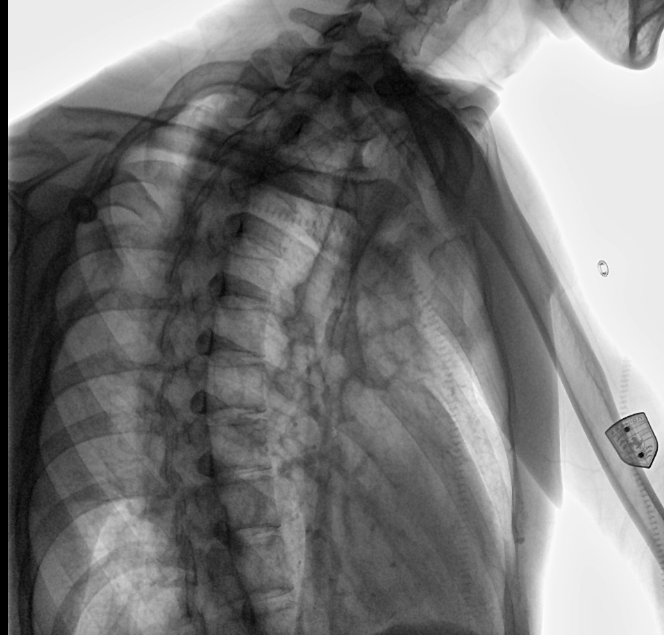

三甲醫(yī)院是依照中國現(xiàn)行《醫(yī)院分級管理辦法》等的規(guī)定劃分的醫(yī)療機構(gòu)級別,是中國內(nèi)地對醫(yī)院實行“三級十等”的劃分等級中的最高級別。而放射科是醫(yī)院重要的輔助檢查科室,是一個集檢查、診斷、治療于一體的科室,臨床各科許多疾病都須通過放射科設(shè)備檢查達到明確診斷和輔助診斷。放射科的設(shè)備一般有普通X線拍片機、計算機X線攝影系統(tǒng)(CR)、直接數(shù)字化X線攝影系統(tǒng)(DR)、計算機X線斷層掃描(CT)、核磁共振(MRI)、數(shù)字減影血管造影系統(tǒng)(DSA)等。與傳統(tǒng)DR設(shè)備不同的是,動態(tài)DR解決了傳統(tǒng)DR盲拍的劣勢,具有可視化操作功能,盡可能的避免誤診發(fā)生,極大的提高了診斷的準確性。動態(tài)DR已不再局限于簡單的拍片功能,而是具有高清快速點片、大幅面透視、造影、動態(tài)影像視頻實時保存回放、自動曝光控制、全身拼接等多種功能。

在過去很長一段時間里,DR設(shè)備的采購一直被進口設(shè)備壟斷。相當一段時間內(nèi),國內(nèi)醫(yī)療機構(gòu)采購影像設(shè)備時,因為近乎苛刻的設(shè)備采購標準,導致國產(chǎn)品牌基本不會被有實力的大型三甲醫(yī)院考慮。三甲醫(yī)院人流量大,且經(jīng)常要面對許多危重、疑難和罕見病例。所以是否有大型三甲醫(yī)院配備自家的產(chǎn)品,成了衡量一家醫(yī)療器械生產(chǎn)企業(yè)實力的特殊標準。接下來器械之家就以安健科技的動態(tài)平板數(shù)字化X射線系統(tǒng)DTP571為例,帶您看看這款國產(chǎn)DR如何突破國外技術(shù)壁壘,在衡水中醫(yī)醫(yī)院中成為一款具有更高臨床應(yīng)用價值的產(chǎn)品。

安健科技動態(tài)平板DR-DTP571

位于衡水市中醫(yī)醫(yī)院的動態(tài)平板數(shù)字化X射線系統(tǒng)DTP571具備高速高清點片功能。這是一款對放射科十分友好的產(chǎn)品。因為它把高速和高清點片結(jié)合,既能方便影像技師有效地抓拍需要的病灶的影像,又能給予影像醫(yī)生清晰的影像進行診斷

為深入了解這款動態(tài)DR,器械之家采訪了衡水市中醫(yī)醫(yī)院的放射科主任醫(yī)師于金厚。

衡水市中醫(yī)醫(yī)院的放射科主任醫(yī)師于金厚主任在放射診斷領(lǐng)域擁有豐富經(jīng)驗,在胸部、腹部及四肢關(guān)節(jié)的X線診斷中有著豐富實踐。

衡水市中醫(yī)醫(yī)院放射科主任醫(yī)師于金厚表示:

作為三甲醫(yī)院,我院對影像設(shè)備成像質(zhì)量都有嚴格的標準要求,尤其是像動態(tài)DR這種比較高端的影像產(chǎn)品,我們曾前往安健的深圳車間進行考察,發(fā)現(xiàn)現(xiàn)階段國產(chǎn)設(shè)備部分功能甚至超過了進口設(shè)備,比如透視回放這一功能,很多進口設(shè)備都沒有這個功能,而且國產(chǎn)設(shè)備操作簡單,非常人性化。設(shè)備的研發(fā)技術(shù)高,如安健的該款設(shè)備探測器就是自主研發(fā)。

設(shè)備的穩(wěn)定性,表現(xiàn)性能方面,我院現(xiàn)在這臺動態(tài)DR,一個上午能夠接待700-800名學生進行體檢工作,如果是使用普通設(shè)備,包含體檢人員脫衣服,擺位置,達到體檢要求在內(nèi),最快檢查速度是2-3分鐘,但沒有透視功能,無法承載這么多的量,而且需要2位醫(yī)師輪換操作。

目前國產(chǎn)DR設(shè)備國內(nèi)產(chǎn)量在8000-10000臺,市場占有率很高,國產(chǎn)設(shè)備現(xiàn)在已經(jīng)能夠和進口設(shè)備比肩,甚至超過進口設(shè)備。身為制造大國,我國的制造工藝、技術(shù)水平已經(jīng)有了很大提高;目前政府主導公立醫(yī)院采購;我們會支持民族工業(yè)。

動態(tài)觀察診斷,實時高清點片

幾乎可以預(yù)見,靜態(tài)DR解決當前中國醫(yī)療市場對于DR設(shè)備的“從無到有”的矛盾,而動態(tài)DR不僅可以解決“從無到有”,更是可以前進一步解決“從有到優(yōu)”的需求。在各省市提升基層醫(yī)療機構(gòu)服務(wù)能力建設(shè)行動中,動態(tài)DR已成為多地集中采購的標的,動態(tài)DR所具備的多功能,不僅能實現(xiàn)基層醫(yī)療市場數(shù)字化DR的普及,更能直接助力基層醫(yī)療機構(gòu)提升多項X線檢查能力。隨著國產(chǎn)DR技術(shù)和服務(wù)的不斷精進與提升,醫(yī)療終端市場DR設(shè)備國產(chǎn)化率將進一步提高,而動態(tài)DR因其多功能與精準診斷特性,將贏得終端用戶的青睞,成為市場的主角。